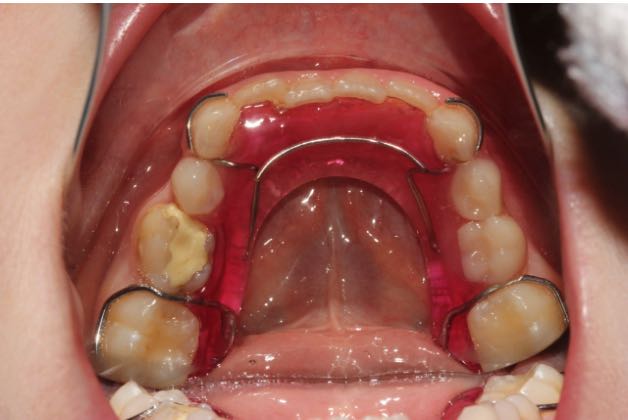

Пластиночные аппараты

Ортодонтические пластины – самый широко известный вид съемных аппаратов. Они могут применяться для детей уже с 8-9 лет. Существует несколько механизмов действий съемных аппаратов, соответственно, они могут применяться в разных клинических случаях.